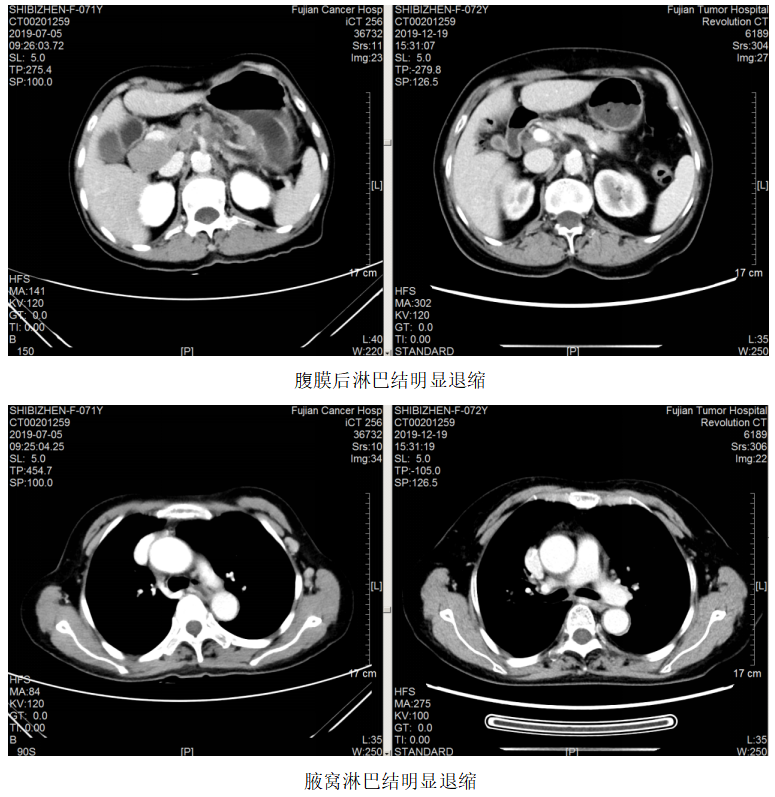

一线治疗:2019.7.12~10.24予FOLFOX方案(奥沙利铂110mg+左亚叶酸钙300mg+5-Fu 2.75)化疗8周期,曲妥珠单抗220mg靶向治疗7次。

疗效评估:PR。

维持治疗:2019.11.6~2022.03.02予方案“卡培他滨+曲妥珠单抗q3w”维持治疗。

2021.5.18开始患者因经济原因改予汉曲优治疗至今,肿瘤进一步退缩,疗效评估PR。

该例患者为胃癌脑转移。脑转移患者的抗HER2治疗一直存在着大分子单抗和小分子TKI之争。有研究显示,由于脑肿瘤部位的血脑屏障受损,通透性要高于正常脑组织,因此曲妥珠单抗可以透过血脑屏障到达病灶部位,尤其是一些接受过脑放疗的病人更是如此。对这例患者,初诊时即存在脑转移,选择了曲妥珠单抗+化疗作为一线治疗,配合脑部放疗,达到PR效果,而后新增脑转移灶,再次放疗,继续曲妥珠单抗治疗,仍达到PR效果,患者前期予赫赛汀,后期因经济原因改予汉曲优,肿瘤依然进一步控制,患者OS>28个月。